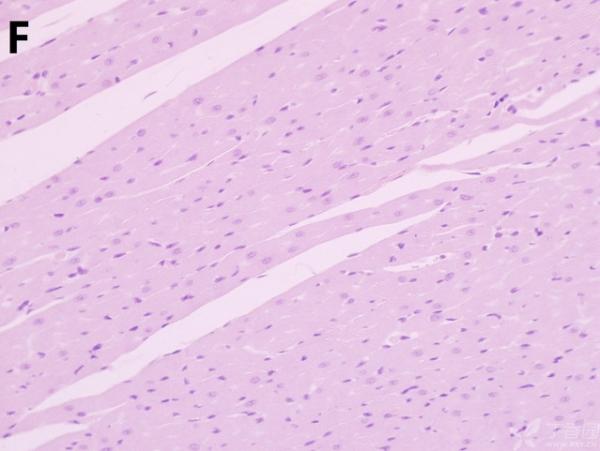

100½ð±Ò·îÉÏ£¬Çë½Ì¸÷λ¸ßÊÖ°ïæ·ÖÎö´óÊóÐļ¡È±ÑªÔÙ¹à×¢HEȾɫʯÀ¯ÇÐÆ¬

ÎÒ½«Ã¿¸ö×éÖ¯ÅÄÁË3¸öÊÓÒ°£¬ÒÔ±ã×ۺϷÖÎö£¬Âé·³¸÷λ°ïÎÒ°ÑA¡¢B¡¢C¡¢D¡¢E¡¢F¡¢GµÄËðÉË´óСÅŸö˳Ðò ÔÙ°ÑA¡¢B¡¢C¡¢H¡¢I¡¢JËðÉ˵ÄÑÏÖØ³Ì¶ÈÅŸöÐò¡£¸ÃÎÊÌâÒ²ÔÚ¶¡ÏãÔ°ÉÏÇóÖúÁË£¬Á´½Óhttp://www.dxy.cn/bbs/topic/23986562 A1.jpg A2.jpg A3.jpg B1.jpg B2.jpg B3.jpg C1.jpg C2.jpg C3.jpg D1.jpg D2.jpg D3.jpg E.jpg F1.jpg F2.jpg F3.jpg G1.jpg G2.jpg G3.jpg H1.jpg H2.jpg I.jpg I2.jpg I3.jpg J.jpg J2.jpg J3.jpg [ Last edited by ÀëÈËÏæÑÅÀá on 2012-10-9 at 21:11 ] |